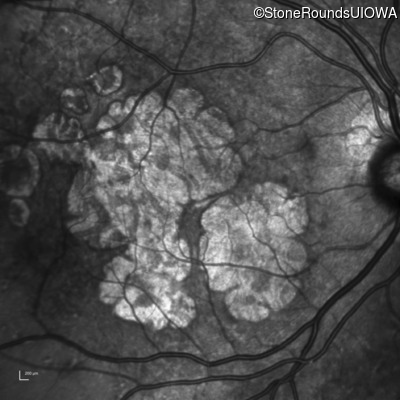

Infrared Fundus Photograph - Left - 20/25 -2

Exemplar